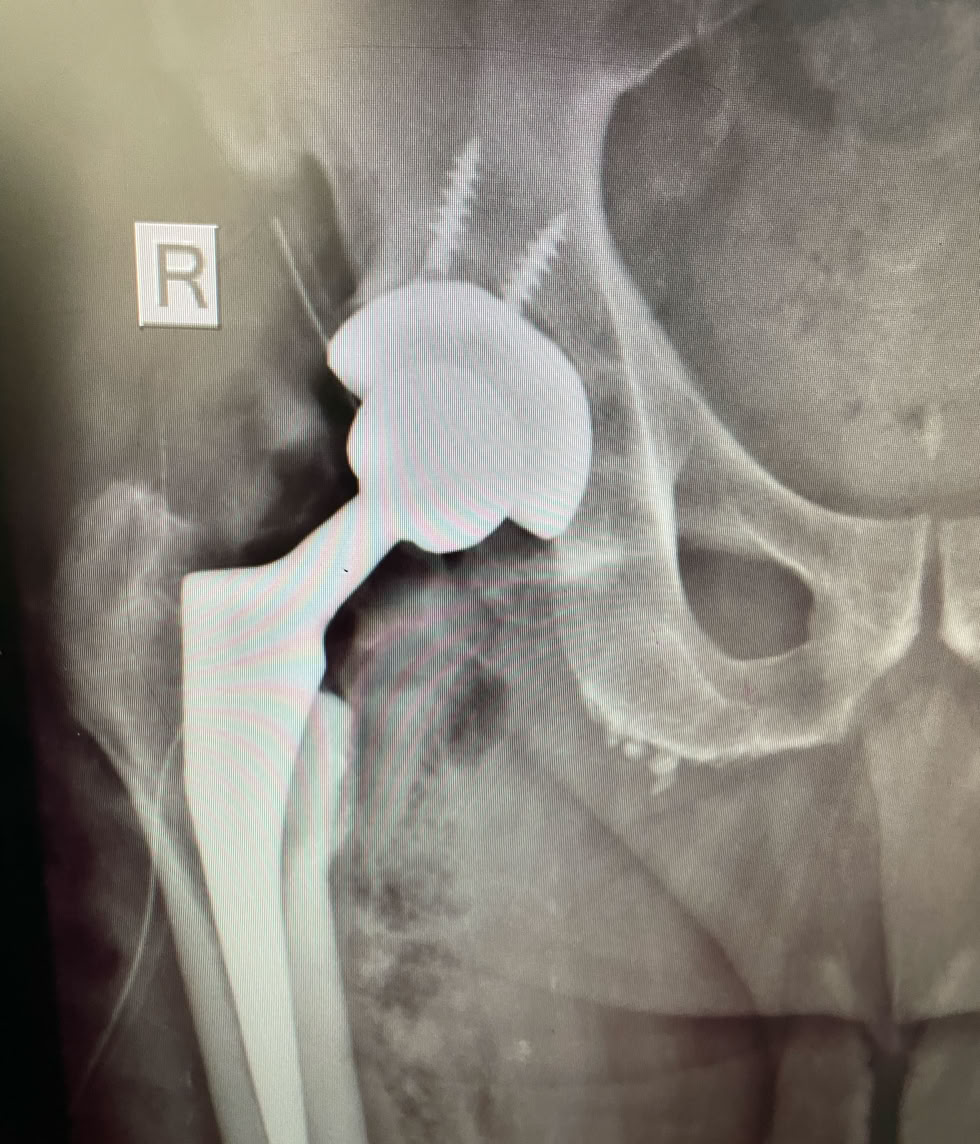

El Dr. Truan, el Dr. Resines y el Dr. Nges con  nuestra instrumentista Marisa Córdoba en una intervención para colocación de  una Prótesis Total de Cadera por una necrosis avascular que le causaba al paciente una gran incapacidad.

Hemos podido hacer una intervención de Prótesis Total de Cadera y una Cirugía Artroscópica .